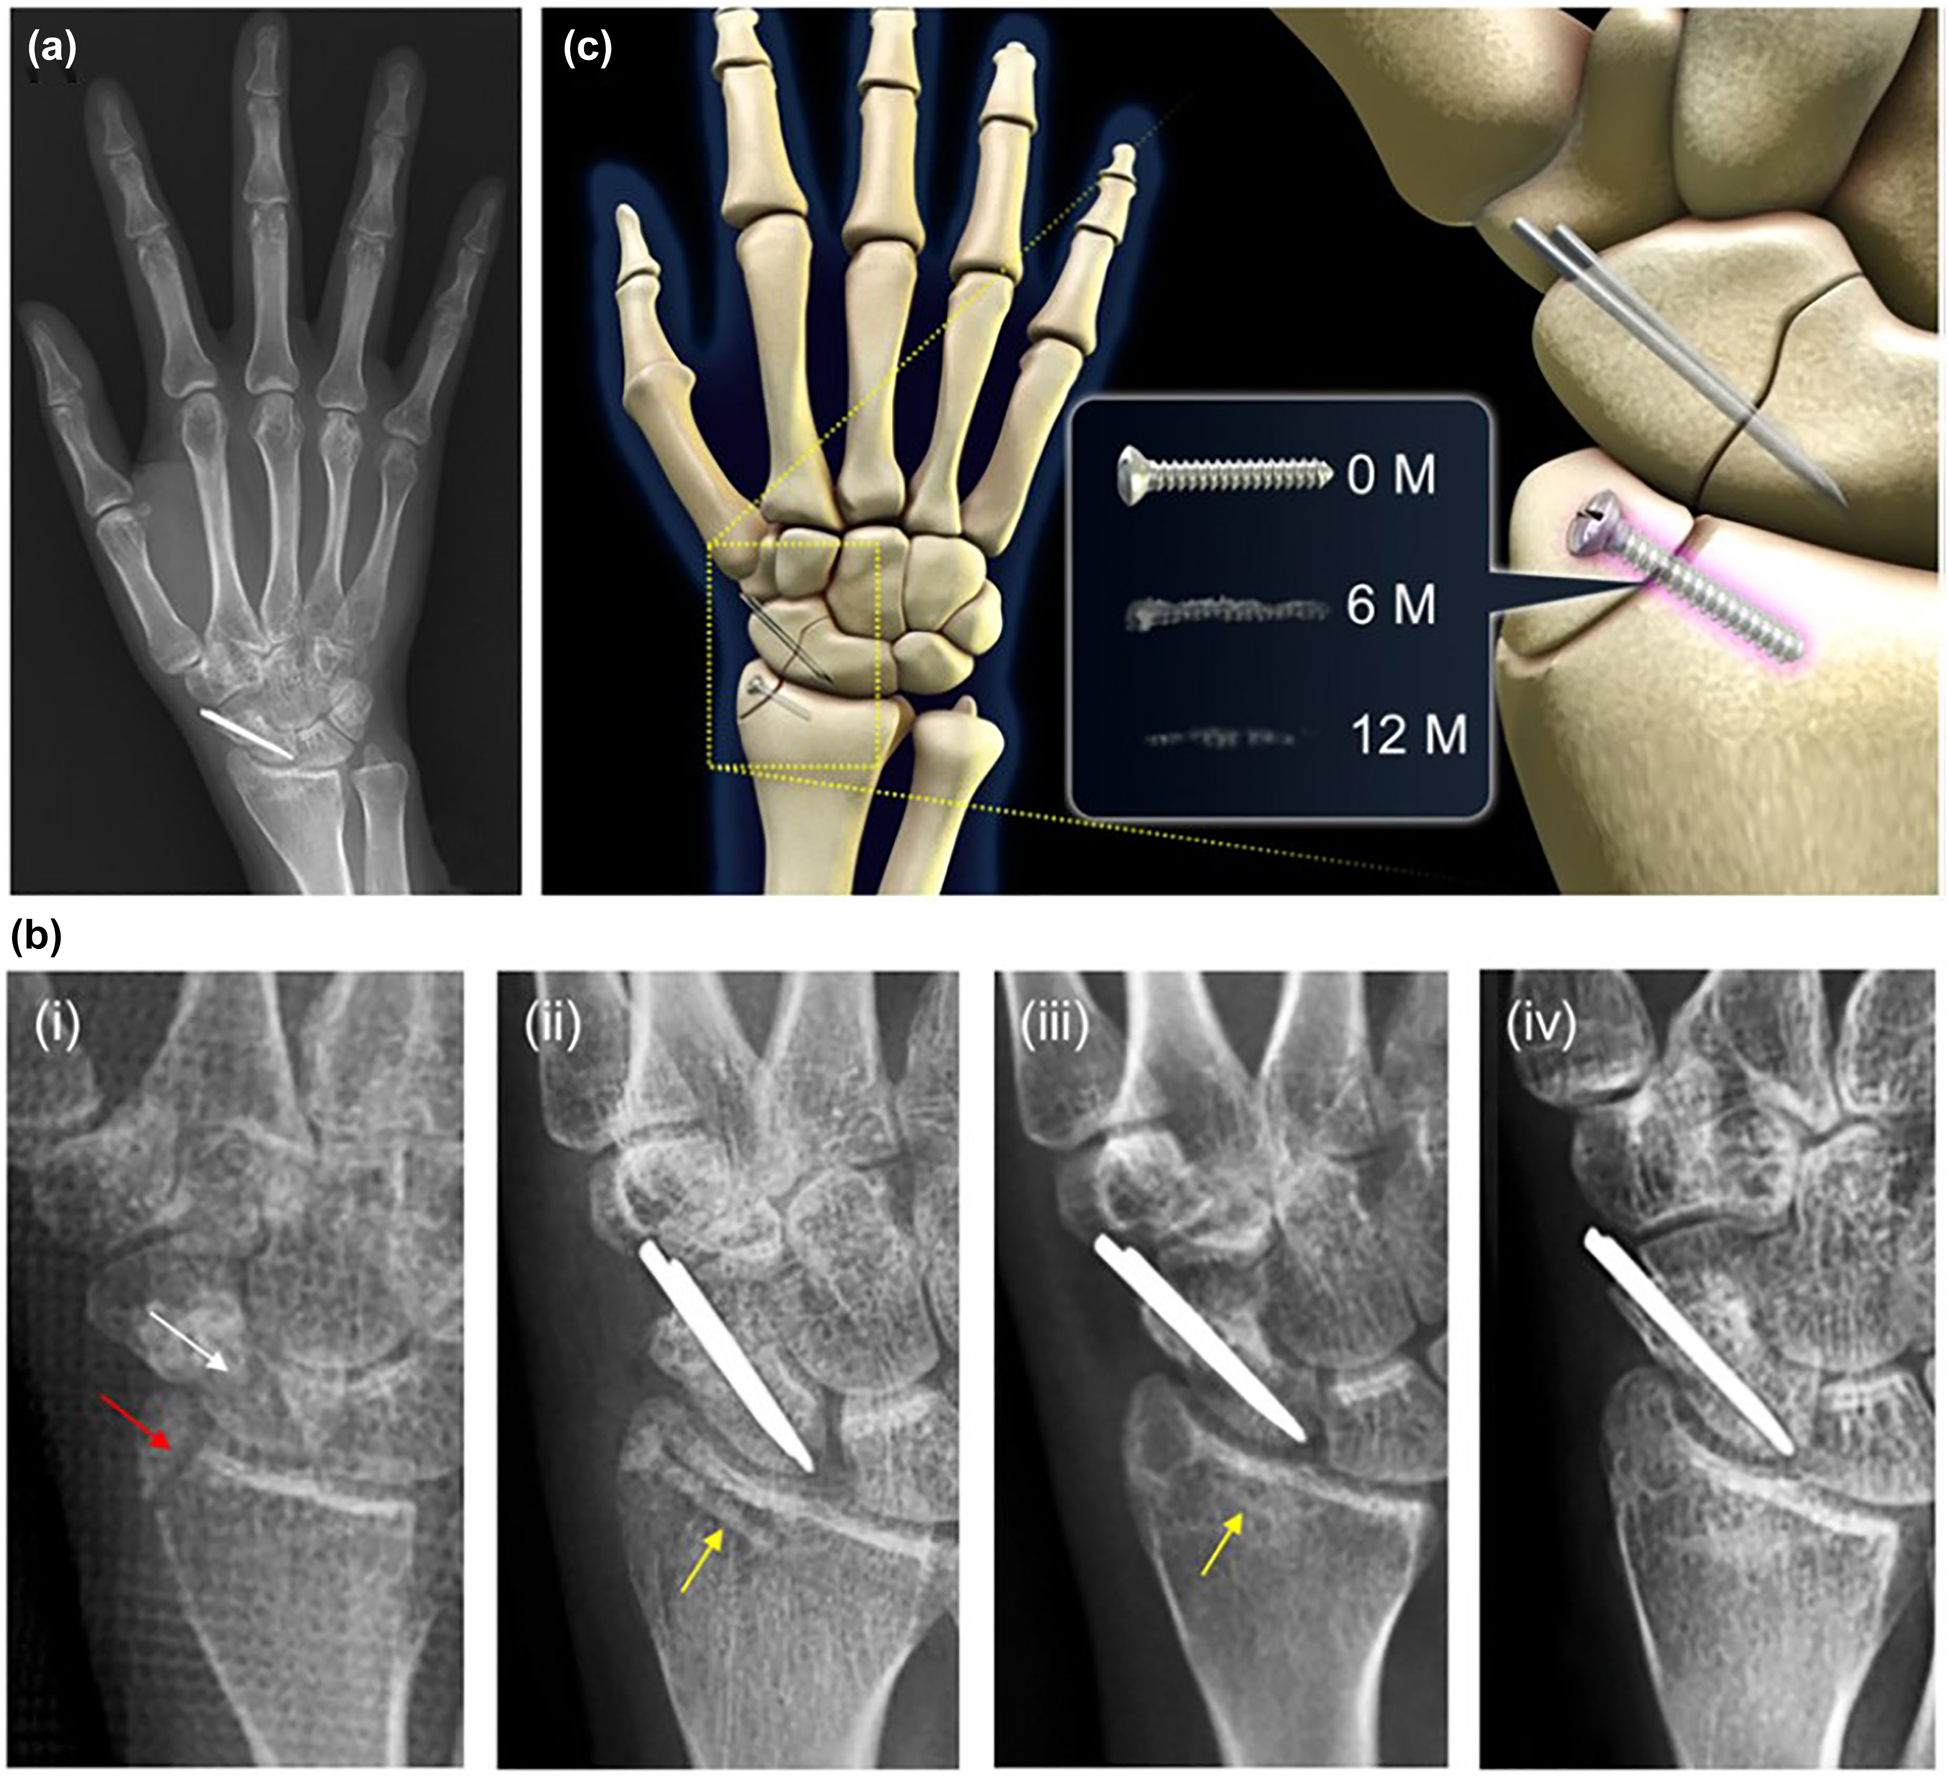

Scroll to top button